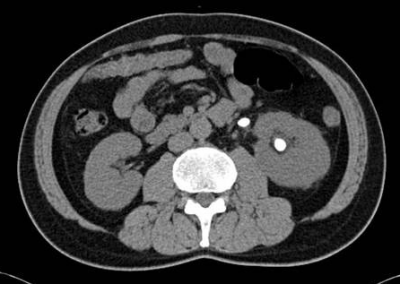

尿所見:蛋白1+、糖(-)、潜血3+、沈渣に赤血球15~30/1視野、白血球1~4/1視野。血液所見:赤血球460万、Hb 14.6g/dL、Ht 46%、白血球8,300、血小板22万。血液生化学所見:総蛋白7.1g/dL、アルブミン3.8g/dL、総ビリルビン1.1mg/dL、AST 35IU/L、ALT 32IU/L、LD 186IU/L(基準176~353)、γ-GTP 45IU/L(基準8~50)、尿素窒素23mg/dL、クレアチニン1.2mg/dL、尿酸8.6mg/dL、血糖92mg/dL、Na 136mEq/L、K 4.0mEq/L、Cl 109mEq/L、Ca 9.2mg/dL。CRP 1.2mg/dL。腹部超音波検査で左水腎症、左腎結石および左尿管結石を認める。腹部単純エックス線写真と腹部単純CTとを別に示す。